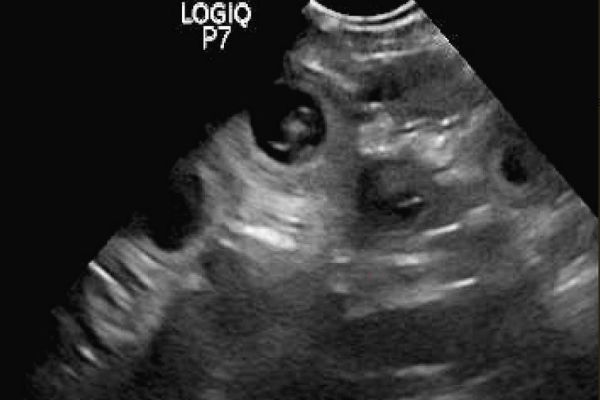

Good News. Tilly hat bereits vor einer Woche ihr süßes Geheimnis gelüftet und gestern haben wir auch bei Stinas Ultraschall einige kleine blinde Passagiere gesehen.